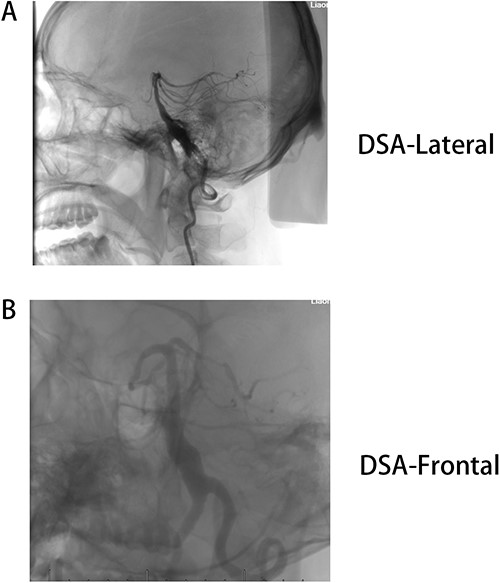

Male, AA, 44 years old, admitted in July 2022 with recurrent pain on the left side of the maxillofacial region for ~1 year. In the last 6 months, the dose of carbamazepine was increased to 300 mg three times daily, but the control of facial pain was still unsatisfactory, so the patient and his family numbers requested to be hospitalized for surgery. The patient had a history of hypertension for ~15 years. The maximum blood pressure was ~200/120 mmHg. The nifedipine controlled-release tablet was used to control his blood pressure by 30 mg daily, which is maintained at ~140/80 mmHg. The neurological examination on admission was unremarkable. TN was assessed as grade V according to the Bar row Neurological Institute classification. Magnetic Resonance Imaging (MRI) of the head suggests small ischemic focus in the pons and cerebellum; marked extending of the basilar artery (Fig. 1A–C). To clarify the etiology, doppler ultrasound of the carotid and vertebral arteries bilaterally revealed no atheromatous plaque or hemodynamics abnormalities. An electrocardiogram and cardiac function and cardiac ultrasound were performed. The results were normal. Biochemical tests for blood cell count, liver function, kidney function, and glucose test revealed no abnormalities. The Digital subtraction angiography (DSA) was given to the patient (Fig. 2A and B). Antiplatelet aggregation therapy with a combination of clopidogrel and aspirin was used before operation. The DSA displayed the VBD, the VBD was length 2.5 cm and width 9 mm, its path was tortuous and deviated to the left. Normal blood flow in the middle venous phase of the imaging was normal. Stent-assisted interventional embolization was chosen. A suitable coil was selected to form basket by EV3 (20 mm*50 cm, Medtronic, USA) and the stent catheter was withdrawn and repositioned through the coil into the right posterior cerebral artery. Release stent 1: LEO (5.5 mm*60 mm, LEO, USA), then choose the appropriate ring (14 mm*30 cm, 13 mm*30 cm, 12 mm*30 cm, 10 mm*30 cm, Taijie Weiye, China) to occlude the dilated artery (Fig. 3A). Postoperatively, we scanned the Computed Tomography (CT) (Fig. 3A), the TN was completely relieved, but there was residual left-sided facial palsy with a House-Brackmann grade IV and a grade III right limb muscle strength. Systematic treatment was operated at the rehabilitation unit, once the condition was stabilized. At 3 months post-operative follow-up the patient showed significant improvement in muscle strength in the right limb, with muscle strength grade V− and significant improvement in facial palsy, which was graded House-Brackmann grade II.

(A) DSA-lateral, (B) DSA-Frontal. Basilar trunk dilation up to 9 mm of diameter and extended over 25 mm of length with a tortuous and deviated path to the left side.